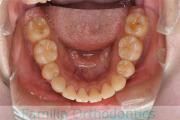

下の前歯が後ろにあるのが気になるとのことで来院されました。非抜歯で行うことも可能でしたが、上下左右から小臼歯抜歯をして治療を行うことをご希望になりました。

マルチブラケット法にて治療を行い、約3年、40回の通院が要でした。

かみ合わせが深い(上の前歯で下の前歯が覆われてしまう)ので、保定をしっかりしないと、また深くなってきてしまいやすいです。